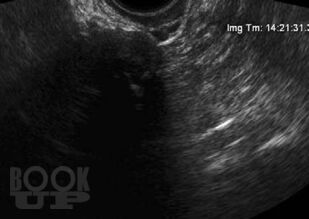

В данном пособии систематизированы сведения об артефактах, которые имеют место при выполнении ультразвуковых исследований. Отдельно рассмотрены эффекты, возникающие в режиме серой шкалы и при выполнении допплеровских исследований. Представлены разработки авторов по изучению допплеровского «мерцающего артефакта» и акустических потоков. Даны рекомендации, позволяющие уменьшить отрицательное влияние артефактов на качество диагностического изображения.